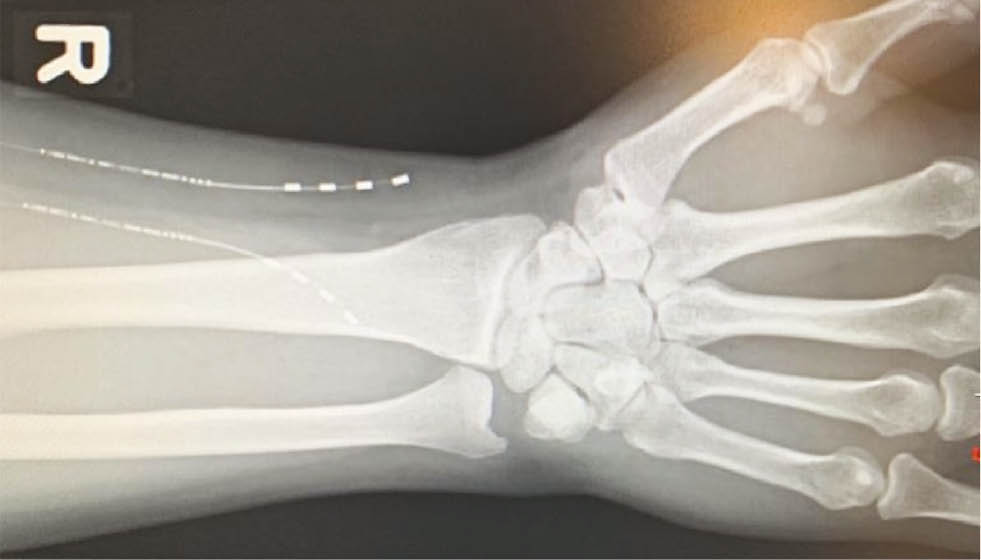

Follow up radiographs of the forearm and hand were obtained to verify the location of the implanted electrodes (Figs. 4 and 5). Both anterior-posterior (Fig. 4) and lateral (Fig. 5) views confirmed appropriate placement of two electrodes along the median and radial nerves.

Fig. 4:

Anterior-posterior X-ray of the forearm demonstrating the location of the implanted electrodes in-situ.